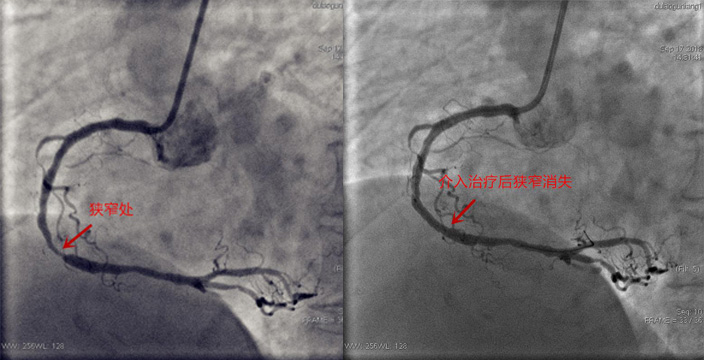

据了解,心脏介入手术是一种新型诊断与治疗心血管疾病技术,经过穿刺体表血管,在数字减影的连续投照下,送入特制的心脏导管,通过心脏导管操作技术对心脏病进行确诊和治疗的诊治方法,它是目前较为先进的心脏病诊治方法,介于内科治疗与外科手术治疗之间,是一种微创的诊治方法。心脏介入相对于外科手术具有多种优势,患者容易接受、损伤小、恢复快,几乎是无痛苦的,“首先这是微创手术,患者创伤小,术后不用卧床,减少痛苦;不用全麻醉,减少麻醉,手术并发症大大减少;费用也较心脏外科搭桥手术相应降低。”王胜文主任说。

“心脏介入的开展,对于长春北部的心肌梗死等心脏病患者是一件好事,患者突发心脏疾病可直接入中医院进行抢救,大大节省了时间。”王胜文主任说,将来要充分利用医疗互联网技术和胸痛绿色通道建设,使患者信息网络实时传递,实现院前急救和院内抢救、各级中医医疗机构转诊及转运网络一体化无缝衔接,开通绿色通道,快速检验、快速报告,诊断明确患者直达介入导管室或重症监护室等措施,降低D-to-B平均时间,挽救病人心肌细胞,改善病人预后,为急性心肌梗死患者搭建起了一条高效通畅的急救“高速路”。

冠脉造影是诊断冠心病的金标准。冠脉造影适应症包括:

1.急性心肌梗死,需紧急冠脉造影并于必要时行冠脉支架植入术,急性心梗静脉溶栓后疗效评估;

2.不稳定型心绞痛包括变异型心绞痛,及稳定型心绞痛,需择期冠脉造影必要时行冠脉支架植入术;

3.陈旧性心肌梗死需择期行支架植入术或冠脉搭桥术者;

4.冠脉支架植入术后或冠脉搭桥术后复查;